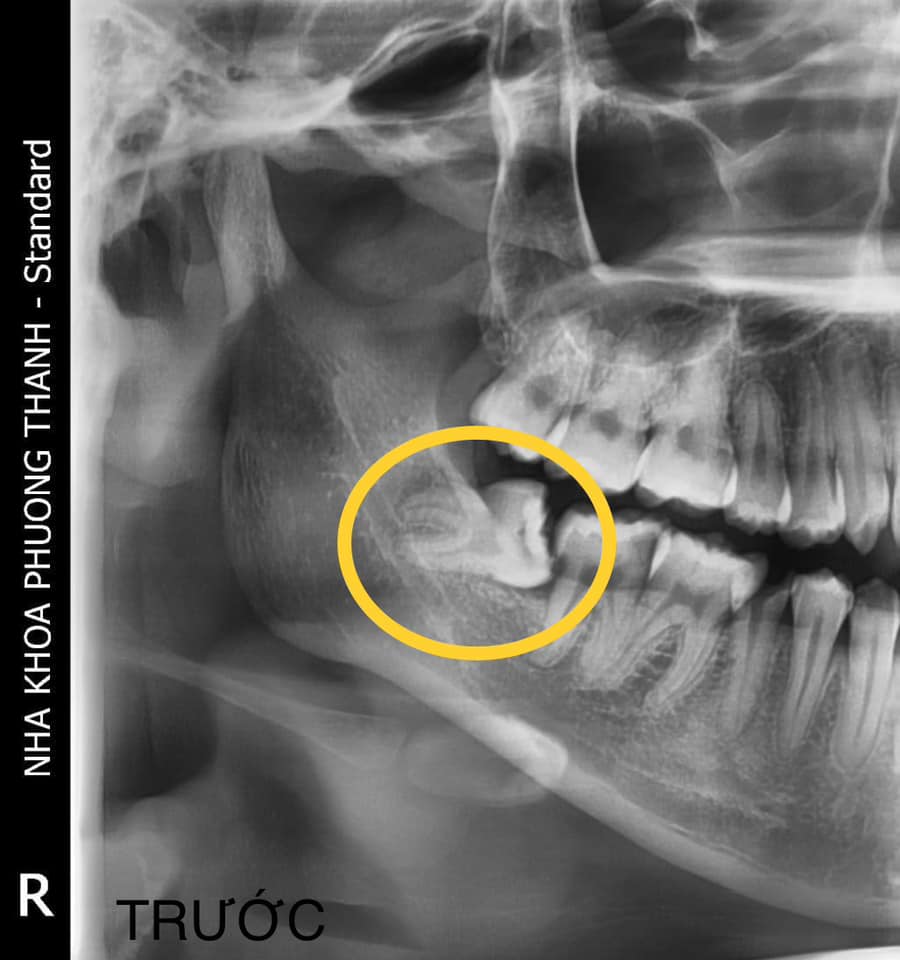

Việc thăm khám và chụp phim giúp bác sĩ đánh giá chính xác vị trí, hướng mọc và mức độ ảnh hưởng của răng khôn, từ đó đưa ra hướng xử lý phù hợp và an toàn hơn.

Thăm khám và điều trị răng khôn tại Nha khoa Phương Thành

Tại Nha khoa Phương Thành, các trường hợp răng khôn sẽ được bác sĩ thăm khám kỹ lưỡng kết hợp với phim chụp đánh giá vị trí răng và cấu trúc xương hàm trước khi đưa ra chỉ định điều trị. Việc kiểm tra đúng thời điểm giúp phát hiện sớm các vấn đề liên quan đến răng khôn và hỗ trợ lựa chọn phương án xử lý phù hợp hơn cho từng trường hợp.